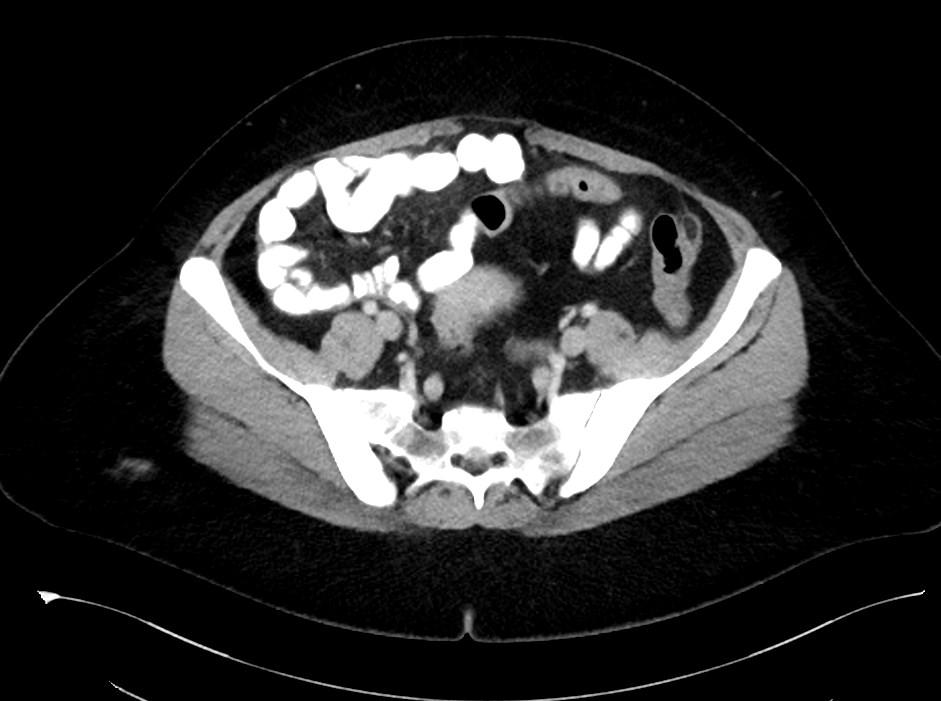

*50-year-old female present with left lower quadrant pain for 3 days.

Answer: Epiploic Appendagitis

MDCT images showed fatty density lesion adjacent to descending colon contains a characteristic hyperdense ring corresponding to thickened visceral peritoneal lining.

Epiploic appendages are small fatty peritoneal projections from the serosal surface of the colon. The inflammation of epiploic appendages can be due to torsion or venous occlusion. The disease is a self-limiting disease. Sonography and CT demonstrate an inflamed fatty lesion adjacent to the colon, including a characteristic hyperdense ring of thickened visceral peritoneal lining on CT [1].